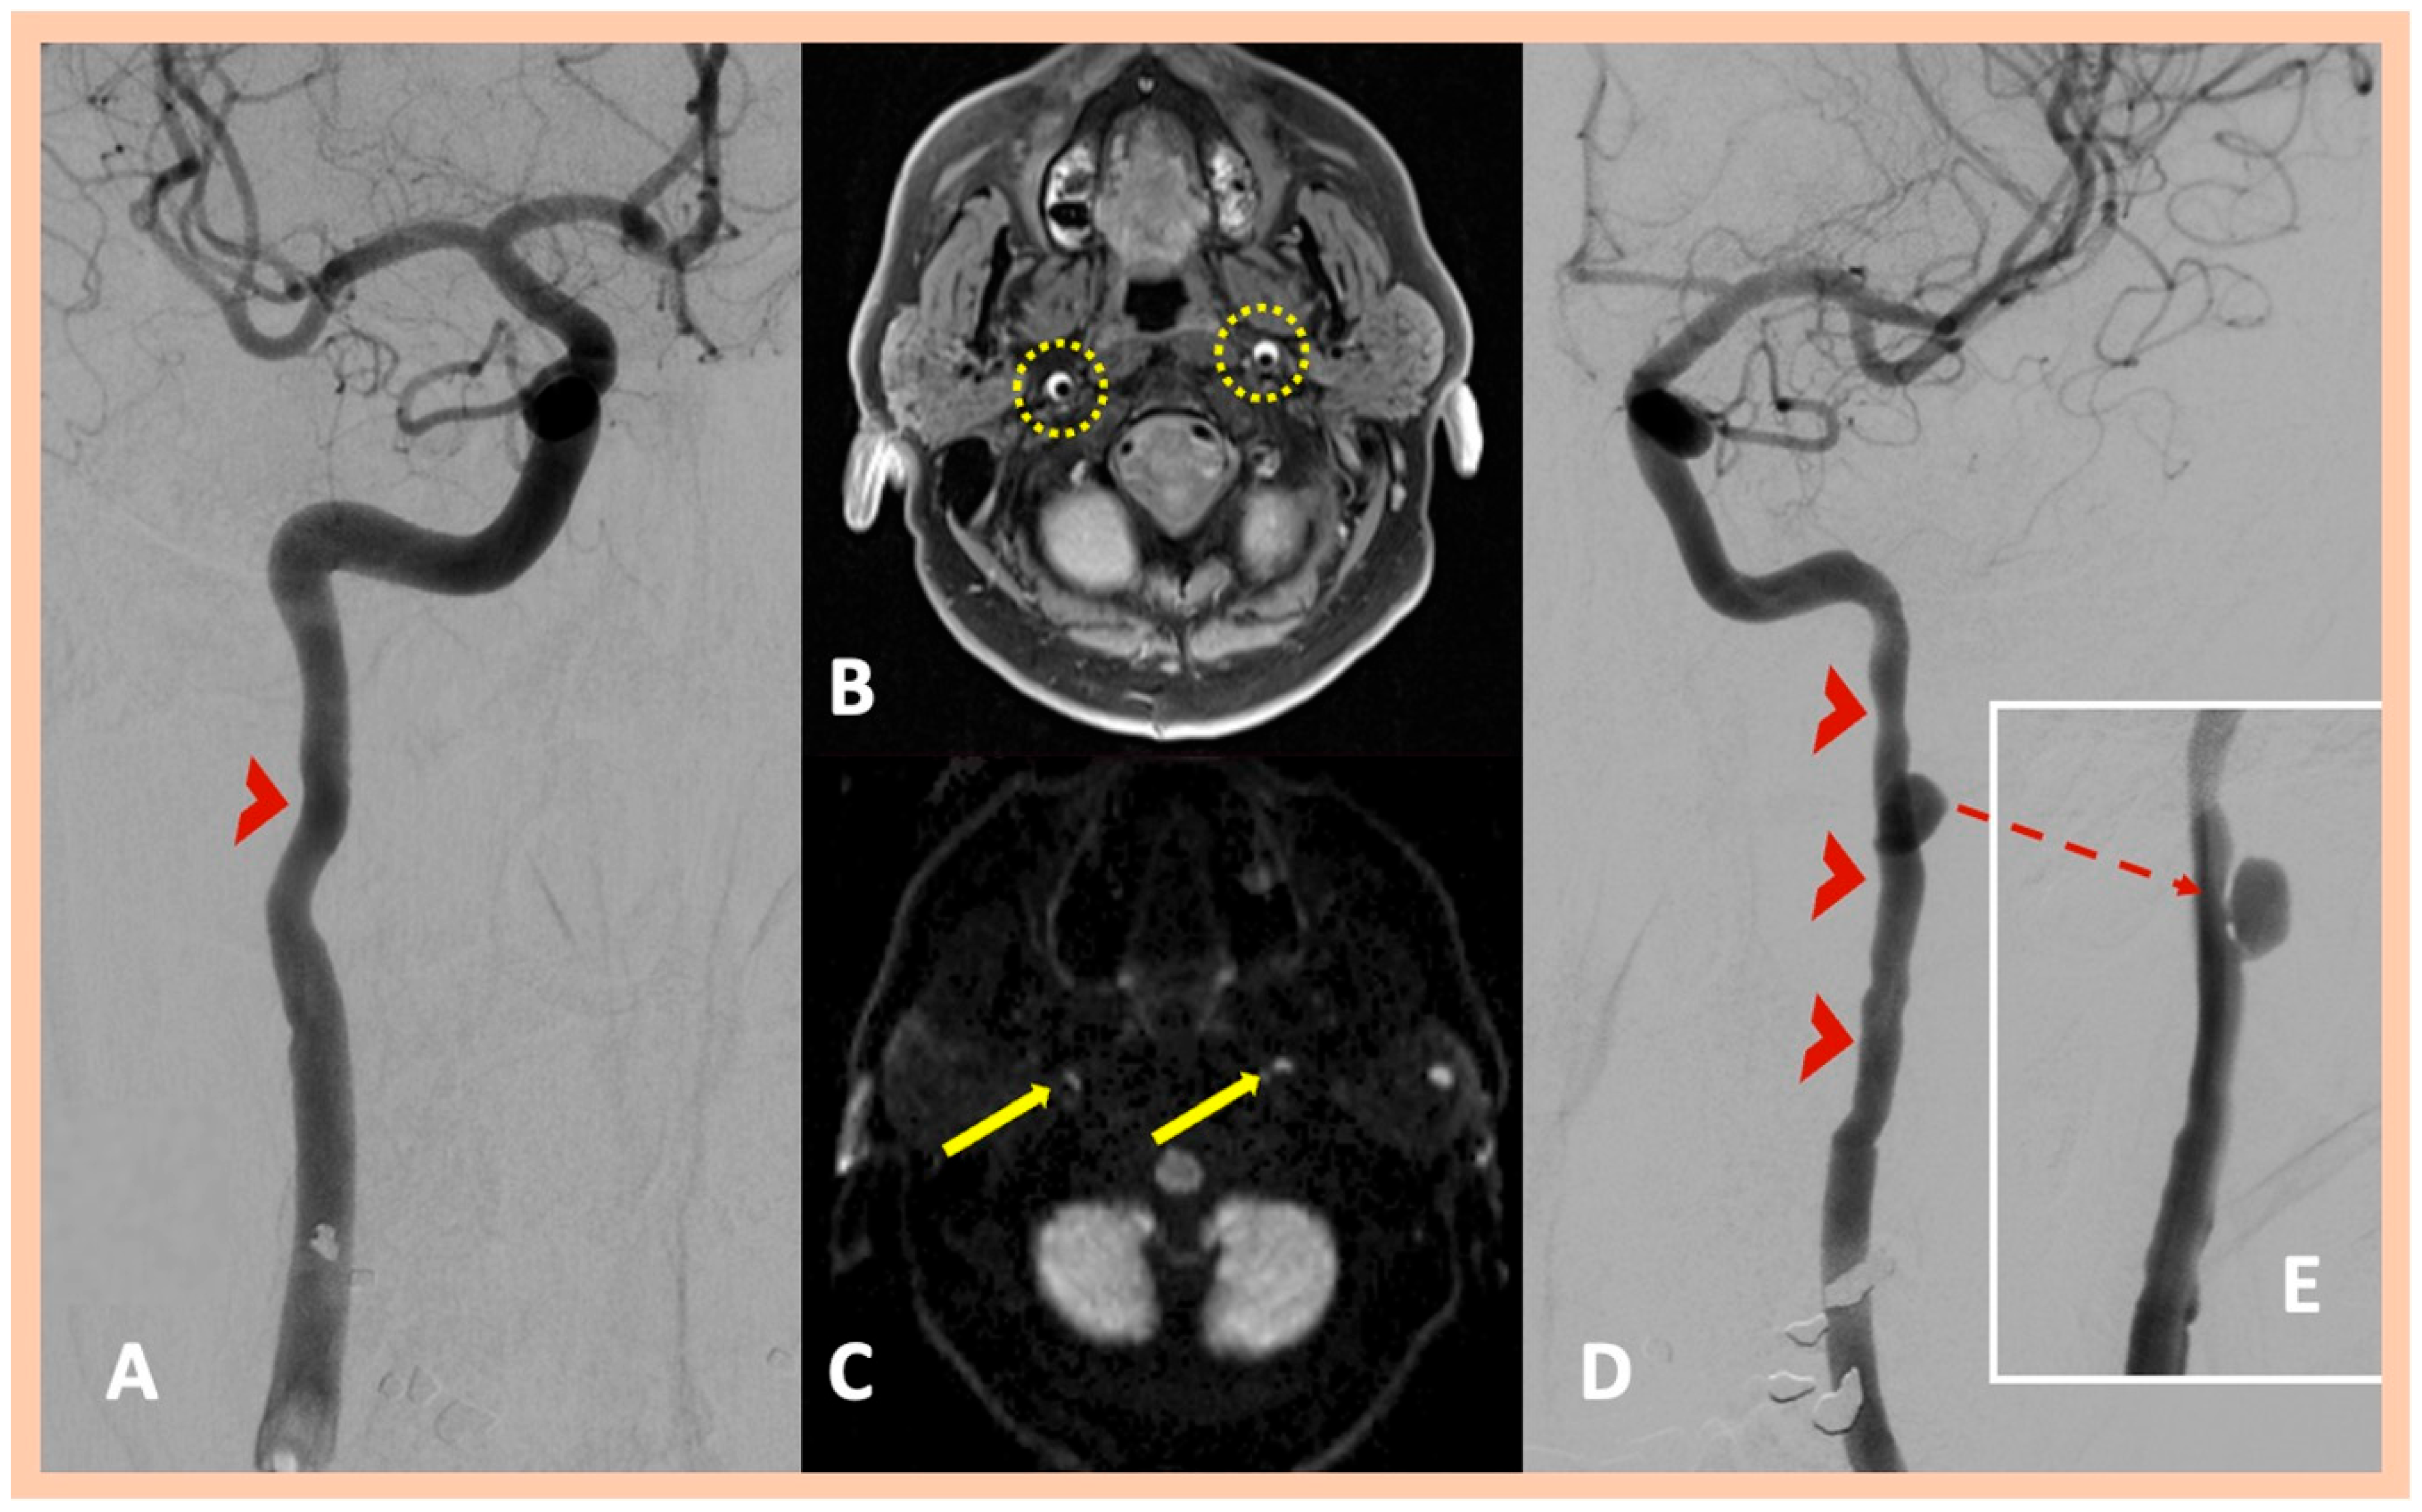

| Pat. #3 | No ischemic lesions | Stenosis along the distal cervical and proximal petrous segments of the left ICA with dissecting pseudoaneurysm along the proximal segment of the left ICA dissection | Intramural hematoma along the distal cervical and petrous segments of the ICA bilaterally | Confirmed MRA findings | Asymptomatic right ICA and symptomatic left ICA dissections | 2 | No |